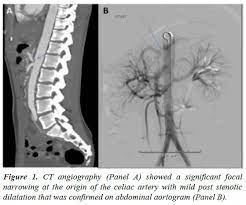

Figure 1 From Celiac Artery Compression Syndrome An Experience In A Single Institution In Taiwan Semantic Scholar